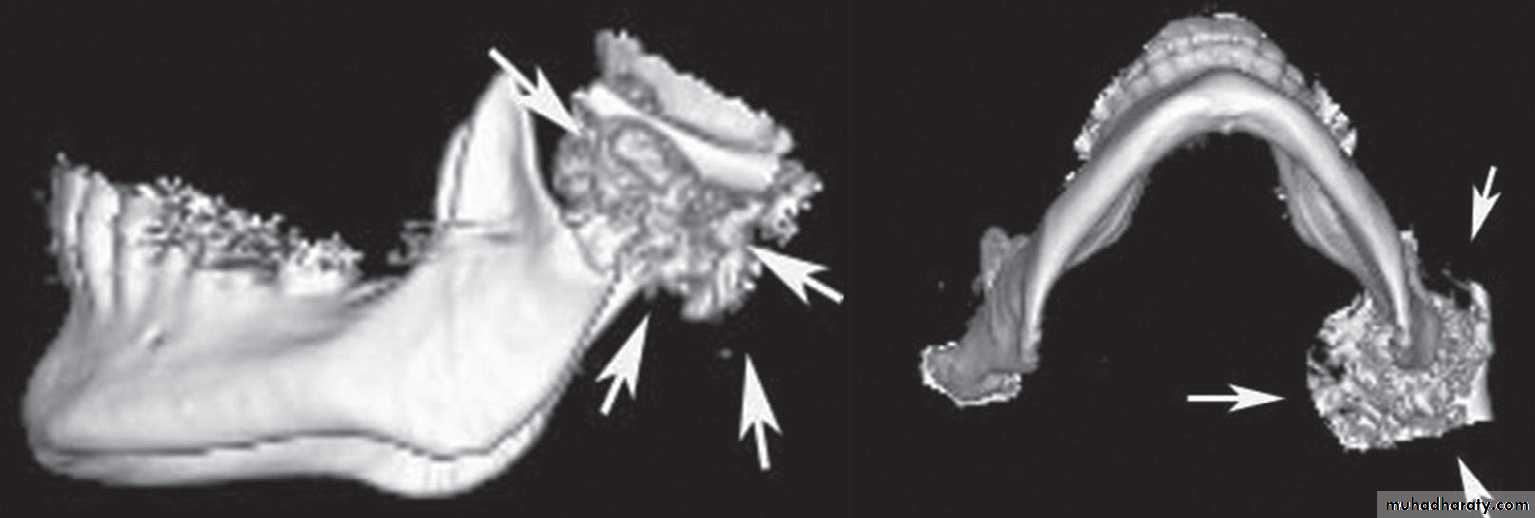

26Ankylosis

Treatment of Temporomandibular Joint ankylosis

Surgery is the only form of treatment for a patient of ankylosis.

• The aims of surgery are to remove the ankylosed mass and create a gap so that mobility of the joint is restored.

• Care has to be taken to prevent re-ankylosis.

• To try to restore the height of the ramus that was lost due to ankylosis.

• If the patient is young, costochondral grafts can be placed to encourage the growth of mandible.

• And most of all to help the patient, to have a chance to live a normal life.

36- Young children with TMJ Ankylosis growth develop mandibular micrognathia.

This is because, the growth center that is present in the condyle is lost.

- To overcome this problem, the joint is reconstructed in a - - way that there is replacement of the growth center with another center. Also there is restoration of balanced mandibular function.

For this purpose, a costochondral graft is harvested.

Ankylosis

Costochondral Graft

This is harvested from the 5th, 6th or the 7th rib. The harvested portion should at least contain 3-4 cm of bone and 1.5 cm of cartilage. Perichondrium and periosteum at the bone-cartilage junction is carefully preserved.• A pre-auricular incision is made.

• The ankylosed mass is removed and the mandible is checked for mobility. Care has to be taken that there is no obstruction in the mandibular movements.

• Then in unilateral cases, the mandible is swung anteriorly and laterally until it correlates with the midline. In bilateral cases, the mandible is advanced until a symmetric face and harmonious profile is achieved.